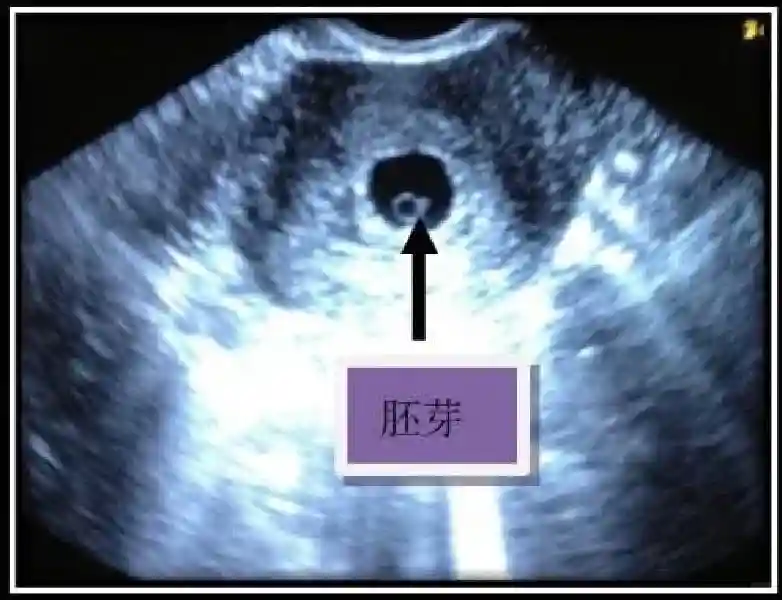

3️⃣胚胎:胚胎通常在6-7周时可以为超声显示,起初为胎芽,表现为卵黄囊一侧局部组织增厚,达到1 -2 mm 时才有可能为超声测量出来。达4-5mm时可见胎心搏动,相应孕周为6-6.5周,妊娠囊大小为13-18mm。胚芽长度≥7㎜时仍未见心管搏动,提示胚胎停止发育。胚胎的出现和妊娠囊直径的关系:妊娠囊直径> 16 mm 时,经阴道超声应显示胚胎。妊娠囊直径> 25 mm 时,经腹超声均应显示胚胎。